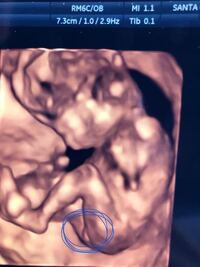

妊娠中のエコー検査、何ヶ月で性別がわかるの? 出典photoAC より確実に性別を知るには? 7 エコー検査での性別判定はかなりの高確率ですが、それでも100%正しいというわけではないのです。 エコー検査で確かめるのが基本! 性別をはっきりと知りたいのなら、妊娠中期や妊娠後期になって 妊娠22週目の女の子のエコー写真 右上がおしり、左下に向かって2本の足が生えています。 こちらはコーヒー豆や葉っぱのような割れ目(シンボル)のようなものが見えるのが分かりやすい写真です。 妊娠25週目の女の子のエコー写真 女の子の証拠エコー「木の葉形」を 41歳5人目にして 初めて知ったJUNなのでした☆ でも思い出してみると 先月に男の子って言われて 「妊娠7ヶ月 エコー 男の子 間違い」 とかいろいろググって見てる時に 「木の葉」ってキーワードは見た気がする

エコー検査で性別が判断できるようになるのは、 早くて妊娠16週目(妊娠5ヶ月目)頃から。 安定期に入った頃です。 男女の性別の特徴が よりはっきりと診断できるようになるのは、 妊娠24週目(妊娠7ヶ月目)に入ってから。 赤ちゃんの性別は、受精した時に既に決定しています。 赤ちゃんの性別を決めるのは、23番目の染色体とされています。 染色体は「XX」と「XY」の2通りの組み合わせがあり、 XXなら女の子 で XYなら男の子 となります。妊娠12週目のエコー写真に見る胎児の特徴|妊婦が注意したい 女の子を妊娠したとき、なにか特徴などありますか? 妊婦 女の子の妊娠兆候は男の子とは違うのか?特徴と違いを調査 ダウン症の可能性のあるエコー写真の特徴は?エコー写真で